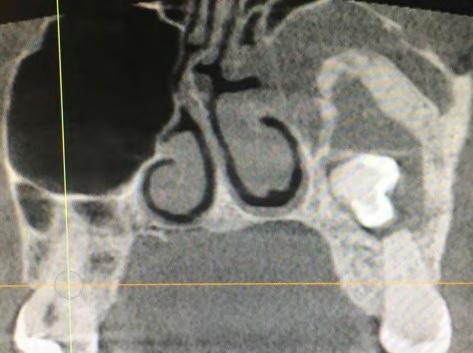

28 An Osteoma Embedding an Ectopic Wisdom Tooth within the Maxillary Sinus A Rare

Kayvan Fathimani, D.D.S., FACS, FRCD(C), FIBCSOMS

Unerupted third molar within maxillary sinus coexisting with maxillary sinus osteoma is extremely rare pathologic finding. Author describes treating patient who presented with this anomaly.

Occurrence